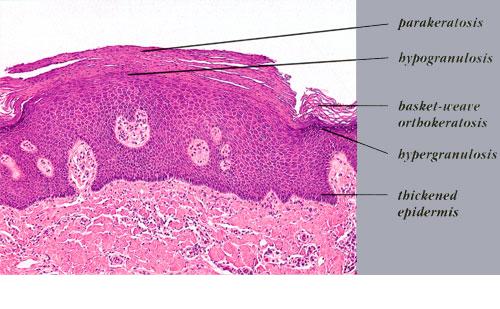

In the localized type, which is present usually but not invariably at birth, only one linear lesion is present. It consists of closely set, papillomatous, hyperkeratotic papules. It may be located anywhere-on the head, trunk, or extremities. Being located on only one side of the patient, it is often referred to as nevus unius lateris . In its configuration, the localized type of linear epidermal nevus resembles the inflammatory linear verrucous epidermal nevus (ILVEN), but the latter differs clinically by the presence of erythema and pruritus and histologically by the presence of inflammation and parakeratosis .

Histopathology.

Nearly all cases of the localized type of linear epidermal nevus and some cases of the systematized type show the histologic picture of a benign papilloma . One observes considerable hyperkeratosis, papillomatosis, and acanthosis with elongation of

The histologic picture of a benign papilloma, as found in most cases of linear epidermal nevus, can also be seen in seborrheic keratosis, verruca vulgaris, and acanthosis nigricans. Even though these four conditions have in common hyperkeratosis and papillomatosis, they can be differentiated easily in typical cases; however, one is occasionally unable to make a diagnosis any more specific than benign papilloma. Thus, in the following three situations, clinical data are required for differentiation from linear epidermal nevus: (a) the hyperkeratotic type of seborrheic keratosis, which is characterized by the absence of basaloid cells and horn cysts and instead shows upward extension of epidermis-lined papillae; (b) old verrucae vulgares, which no longer show vacuolization of epidermal cells or columns of parakeratosis ; and (c) acanthosis nigricans showing more pronounced acanthosis and greater elongation of the rete ridges than usual .